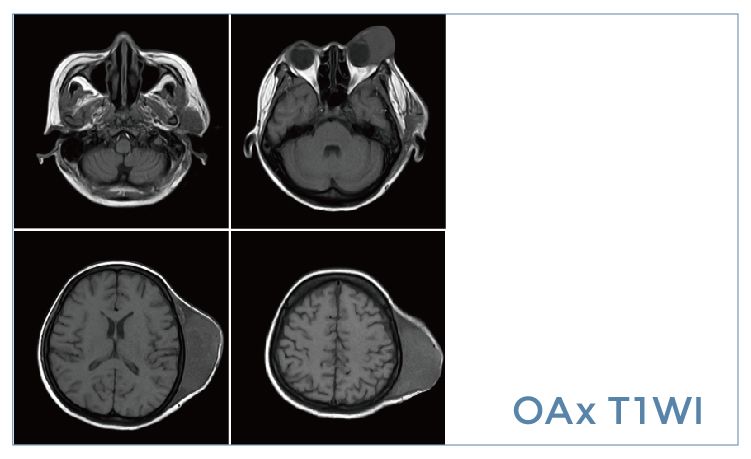

【朗润影像档案】20191018磁共振影像病例结果讨论

【朗润影像档案】磁共振影像病例分享(编号20191018)